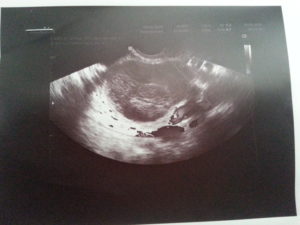

УЗИ снимок кисты желтого тела.

- УЗИ. В полости кисты отсутствуют кровеносные сосуды. Это является отличительной характеристикой лютеинового новообразования.

Уточнить диагноз позволяет УЗИ.